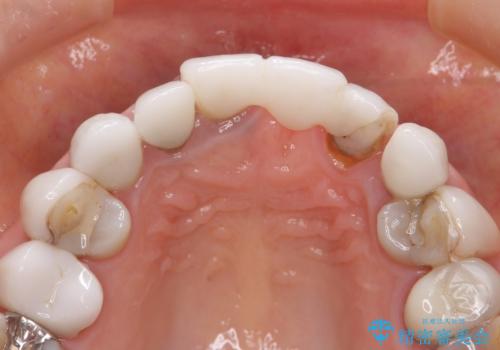

[ セラミック治療 ] 歯ぐきの際の黒ずみを改善したい

- 歯ぐきとセラミックの間の黒ずみが目立つので、きれいに治してほしい。と希望され来院されました。

歯ぐきの位置が変化しクラウン下の歯が見えるようになってしまったことで、審美障害が生じている状態です。

クラウンマージンの再設定を行うことで、黒ずんだ部分を再度覆い、審美障害を改善します。

- 52.8万円(ジルコニアクラウン×4・仮歯×4)費用は治療当時の料金となります